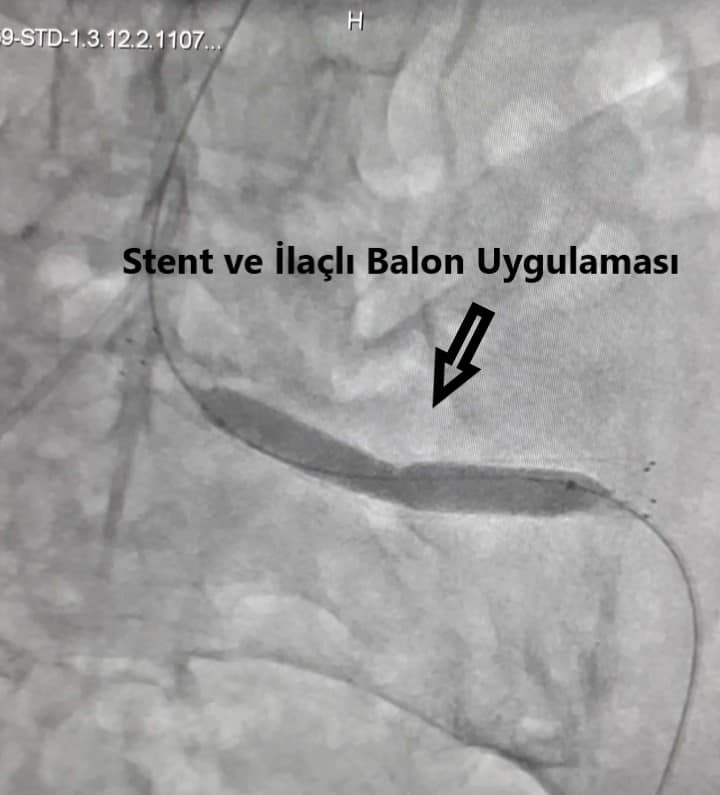

Op. Dr. Görkem Yiğit yaptığı açıklamada; “Ölümcül durumlara yol açabilen karın ana damarı ve bacağı besleyen damarlardaki balonlaşmalar (abdominal, iliak aort anevrizmaları) oldukça önem arz eden ve Kalp Damar Cerrahisi branşını ilgilendiren hastalıklardır. Sinsice ilerleyen, genellikle 65 yaş üzerinde, tansiyon hastalığı olan ve sigara içen bireylerde görülebilen bu hastalık, patladığında ölümcül bir tabloya yol açabilir. TKDCD (Türk Kalp ve Damar Cerrahisi Derneği), tüm yurt genelinde başlattığı “İçinizdeki Balon” adlı projesi ile bu konunun önemini vurgulamaktadır. Açık ameliyat ve kapalı yöntemlerle erken müdahale edilebildiğimiz bu önemli hastalık açısından, patlama noktasına gelmeden, Kalp ve Damar Cerrahisi polikliniklerine erken tetkik ve görüntüleme yöntemleri açısından başvurabilirsiniz.82 yaşında erkek hastamız, poliklinik başvurusu sonrası karın içerisindeki bacak ana atardamarında 5 x 5 cm çapında balonlaşma tespit edildi. Yaşı ve ek hastalıklarından dolayı açık cerrahi ameliyatı kaldıracak durumda değildi. Patlama riskinden ötürü aynı gün içerisinde hastanın yatışı yapılarak, kapalı yöntem ile hastaya anestezi verilmeden anjiyografi ünitesinde İliak Stent + İlaçlı Balon uygulaması başarıyla yapıldı” dedi.